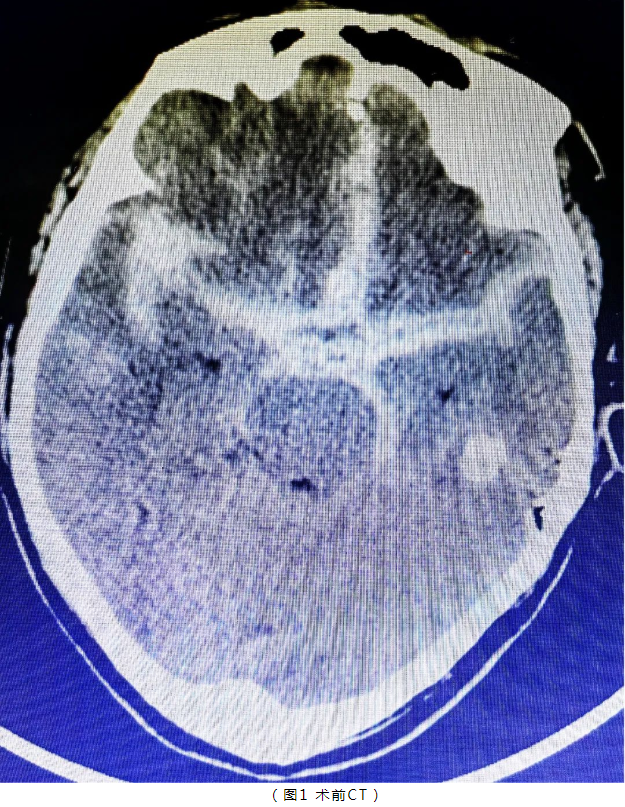

年过六旬的张X(化名)平素身体硬朗,但入院前2小时突发剧烈头痛伴言语不清,继之出现意识不清、烦躁不安。刚入院时格拉斯哥评分13分,Hunt-Hess分级3级。急诊行头颅血管成像(CTA)检查后,根据提示,医师团队考虑前交通动脉瘤破裂伴自发性蛛网膜下腔出血可能性大,急诊行全脑血管造影术。

造影术中见前交通有一囊性凸起,结合蛛网膜下腔出血重、临床症状进展快的特点,考虑前交通血泡样动脉瘤,血泡样动脉瘤多见于颈内动脉床突段,而前交通血泡样动脉瘤极为罕见。该类动脉瘤瘤壁菲薄,仅被血凝块、纤维组织或动脉外膜覆盖,缺乏内膜、弹力层、中层及胶原组织,动脉瘤再次破裂性大,若不手术干预,患者再发出血及死亡率高,因此该类病人总体预后差。我院神经外科本着“厚德、至善、精业、进取”的精神,神经外科医师团队迎难而上开展了微创介入手术治疗。